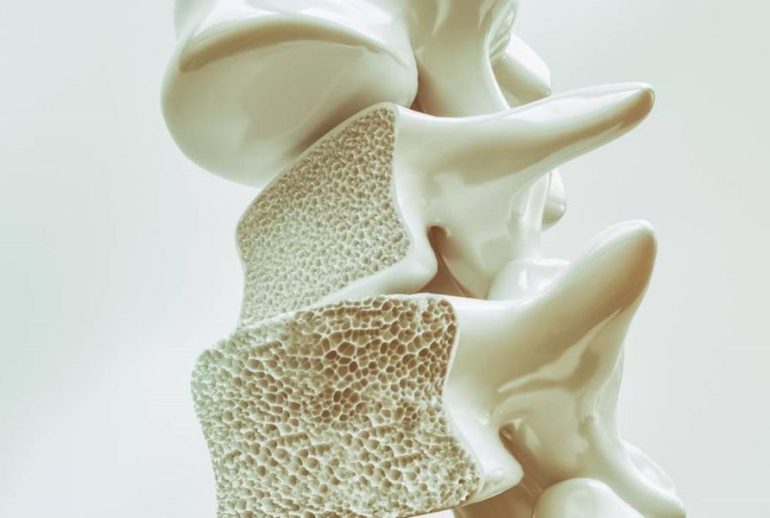

استئوپنی به معنای کاهش تراکم استخوان است. در این وضعیت، استخوانها ضعیفتر از حالت طبیعی میشوند، اما هنوز به مرحله پوکی استخوان نرسیدهاند. استئوپنی را میتوان مرحلهای بین سلامت استخوان و پوکی استخوان در نظر گرفت.

- شکستگیهای مکرر: خصوصاً در استخوانهای مچ دست، لگن یا ستون فقرات

- کاهش قد: کوتاه شدن قد میتواند نشانهای از فشردگی مهرهها باشد

- درد مزمن استخوانی: درد مداوم در استخوانها، بهویژه در کمر و گردن